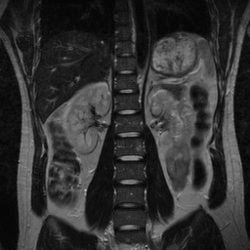

因为人的体内存有大量的水分子,而水分子中还有氢原子,sMRI其实就是利用氢原子来成像,这意味着人身体中的内脏、软组织等含有高水分与脂肪的器官会被清楚的扫描出来,而大脑就是这样的一个器官,通过sMRI可以清晰的看到大脑中的密集结构与大量细节,但sMRI的成像无法观察到大脑的运动情况,即无法判断那些部位目前是比较活跃的,只能给出大脑的结构细节。

如下图,科学家利用sMRI对人体腹腔进行成像,从图可以看出,腹腔的结构很明显。